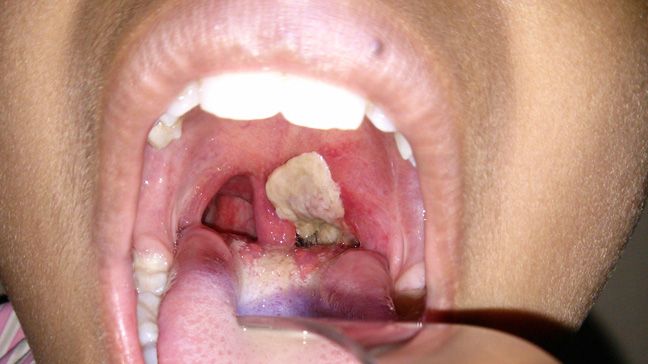

Diphtheria is a serious bacterial infection usually affecting the mucous membranes of your nose and throat. It typically causes a sore throat, fever, swollen glands and weakness. Appearance of a sheet of thick, gray pseudo-membrane over the back of your throat and nose is its hallmark. This membrane can block your airway, causing you to struggle for breath.

Diphtheria signs and symptoms often appear within two to five days of exposure to the infection. The bacteria release toxins that spread through your bloodstream and often cause a thick, gray adherent membrane (pseudomembrane) to cover your tonsils, pharynx, and/or nasal tissues. Other common symptoms include:

Though the thick gray coating on your throat or tonsils is diagnostic enough, they might take a sample of the affected tissue and send it to a laboratory for testing to confirm the diagnosis.